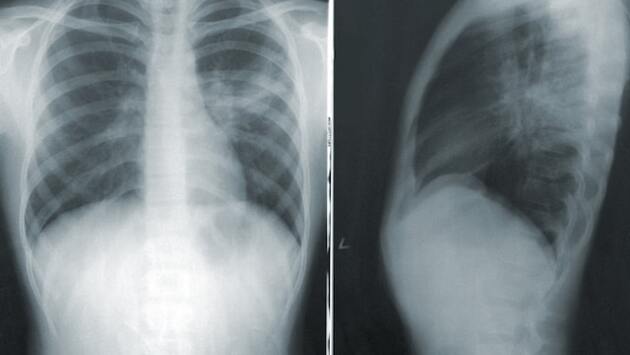

Физиатр Богородская: люди с иммунодефицитом подвержены заражению туберкулезом

Доктор медицинских наук и физиатр Елена Богородская назвала категорию людей, подверженных заражению туберкулезом. Об этом сообщает РИА Новости.

Медик отметила, что в зоне риска находятся люди с иммунодефицитом, так как они могут заразиться даже при единичном контакте с больным человеком.

Она посоветовала больным носить средства индивидуальной защиты, так как это значительно снижает риск для окружающих. Если с человеком, зараженным туберкулезом, долгое время контактировал человек без иммунодефицита, то он также оказывается в зоне риска заражения.

Богородская напомнила, что инкубационный период туберкулеза может длиться от двух месяцев до 60 лет. У большинства пациентов первые симптомы появляются спустя пять лет после заражения.